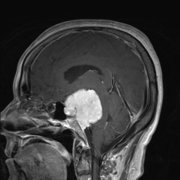

【松果体肿瘤】松果体区肿瘤能

松果体悬挂在大脑的正中央。18世纪法国科学家勒内笛卡尔认为松...